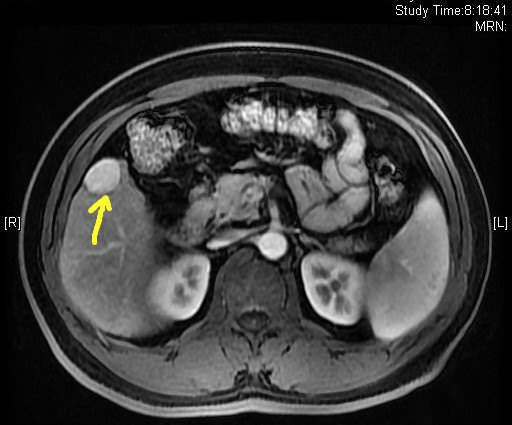

这个病人有点难度。男性,52岁。有多年乙肝病史,平时饮酒无度,检查核磁发現,他的肝脏严重肝硬化,肝右前叶发现一个核桃大小的肿瘤,准备手术前,仔细分析片子,发现因肝硬化肝内有多发的硬化结节,这些结节中会不会还有其他肿瘤病灶同时存在?直觉告诉我问题没这么简单。

如果肝癌是多灶的,匆忙切除这个可见肿瘤之后,那些暂时看不到的微小潜在病灶在术后不久就会显现出来,到那时患者不仅为一次没有彻底治疗的手术付出代价,微小病灶还会因为术后全身免疫功能下降而迅速生长和扩散。

术前必须搞明白,立马做DSA,果真发现另外两个微小病灶,一个在8段,一个在5段,随即做了TACE,将三个病灶全部栓塞。一周后在CT引导下我用射频将三个病灶全部毁损,效果很不错。